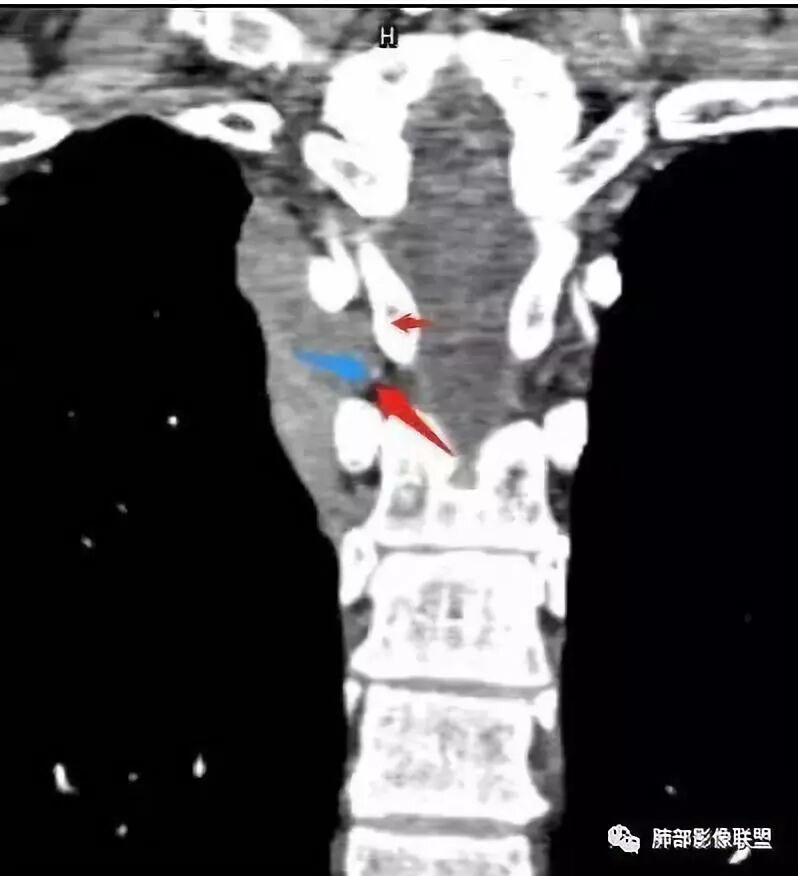

南边: 这是病灶吗

南边: 上面可能与锁骨伪影干扰有关

南边:

南边:   倾向于纵隔,神经源性肿瘤

答:神经源性肿瘤的解剖位置及形态很重要—沿神经干方向生长走行。后纵膈内神经鞘瘤最常见的是神经根出入椎间孔处,并可沿着肋间神经方向分布,所以后纵膈神经鞘瘤通常横径大,上下径小,这个病例明显上下径长,所以不符合神经鞘瘤;神经节细胞瘤可沿着椎旁上下方向分布(参见上图黄色梭形的神经节),所以表现为上下径长,虽然生长方式符合,但是节细胞瘤以粘液为主,易钙化,该病例成分及强化方式不符合。

病灶内的肋间动脉穿行代表什么?

答:代表病灶内供血血管或病灶具有侵袭性将血管包绕其中。提示病灶的肺外来源属性。